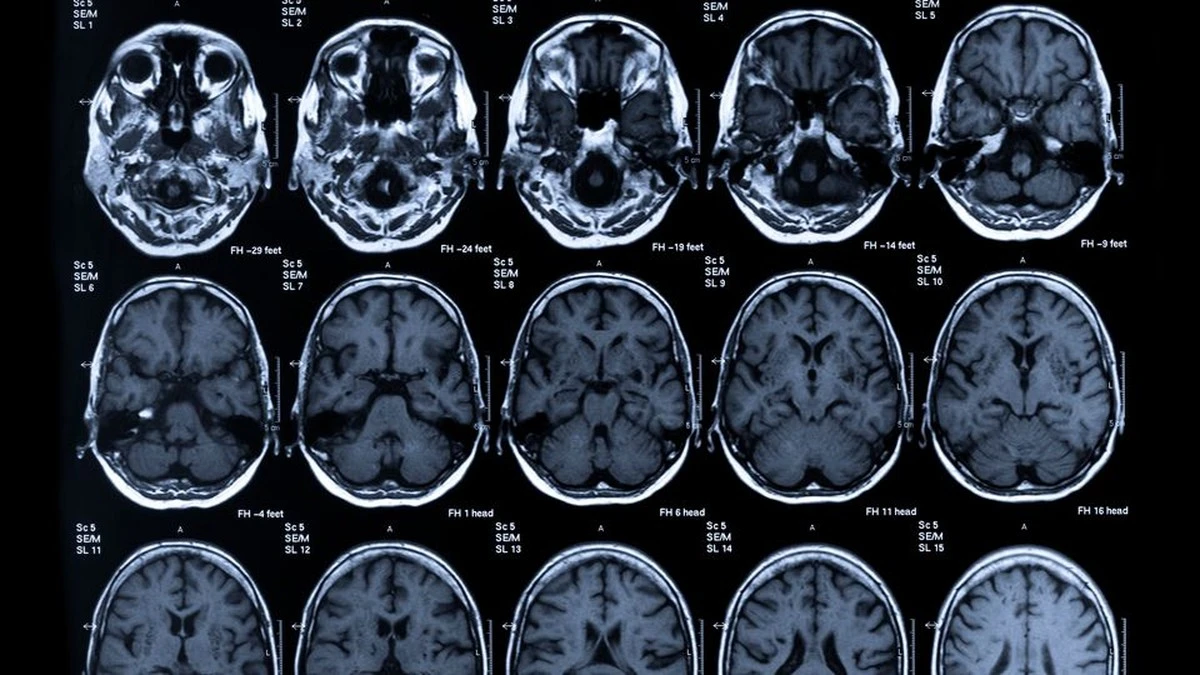

Wo liegt der Fehler? Die Wissenschaftler haben die Gehirne während dieser Entscheidungen gescannt (mittels fMRT) und eine Region ins Visier genommen: den ventromedialen präfrontalen Cortex. Das ist der Bereich, der eigentlich Bewertungen und Entscheidungen miteinander synchronisieren soll.

Was haben sie beobachtet? Bei jenen, deren Handeln und Urteilen am stärksten auseinanderklaffte, arbeitete dieser Cortex während eigener Entscheidungen auffällig träge. Er kommunizierte schlechter mit den Kontrollzentren des Gehirns. Stellen Sie sich das vor wie eine schlecht funktionierende Filteranlage: Das moralische Signal kommt an, aber die Umsetzung im Hirn stoppt.